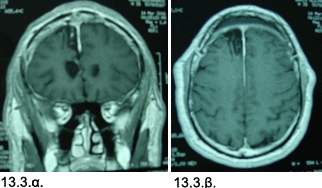

Εικόνες 13.2.α. & 13.2.β. Απλή ακτινογραφία που δείχνει την διάταξη των καταγραφικών ηλεκτροδίων στη κεφαλή (13.2.α.) και τμήμα του διεγχειρητικού ηλεκτροεγκεφαλογραφήματος που δείχνει τις αιχμές που υποδηλώνουν την έναρξη της επιληπτικής κρίσεως, στο δεξιό μέρος του γραφήματος (13.2.β.).

Επεμβατική αντιμετώπιση: Κατόπιν αυτών, έγινε διερεύνηση με υποσκληρίδιο πλέγμα ηλεκτροδίων και βαθέα ηλεκτρόδια, με κάλυψη όλων των πιθανών επιληπτογόνων εστιών στους δύο μετωπιαίους λοβούς. Κατά το επεμβατικό Video-ΗΕΓ, καταγράφηκε πολλά υποκλινικά ή «ηλεκτρικά» επεισόδια, και προσδιορίσθηκε μία κωνοειδής «πηγή» των επιληπτικών κρίσεων, στον πόλο του δεξιού μετωπιαίου λοβού, που περιελάμβανε το έσω 1/3 της πρόσθιας επιφάνειας, το πρόσθιο έσω 1/3 της κάτω επιφάνειας και τμήμα της πρόσθιας έσω επιφάνειας.